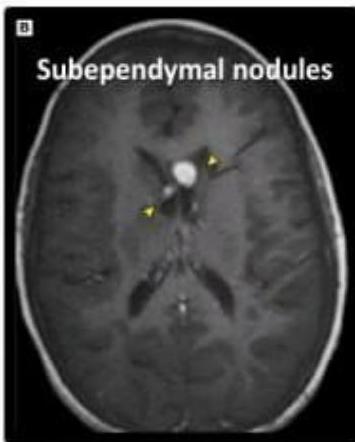

- Subependymal Nodules: Calcified nodules adjacent to lateral ventricles (Hamartomas).

- Subependymal nodules